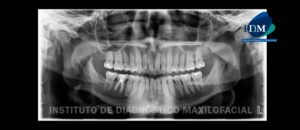

244 – Síndrome Yugular de Eagle

El alargamiento del proceso estilohioideo está históricamente asociado con dos variantes del síndrome de eagle. En 1937, Eagle propuso dos síndromes asociados con un proceso